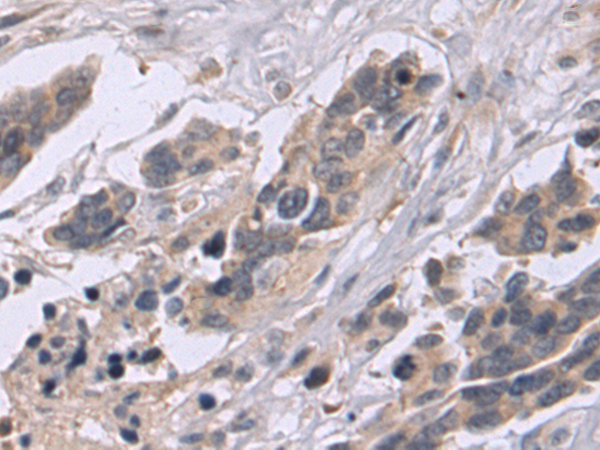

IHC positive control: |

Human colorectal cancer |

IHC Recommend dilution: |

50-100 |